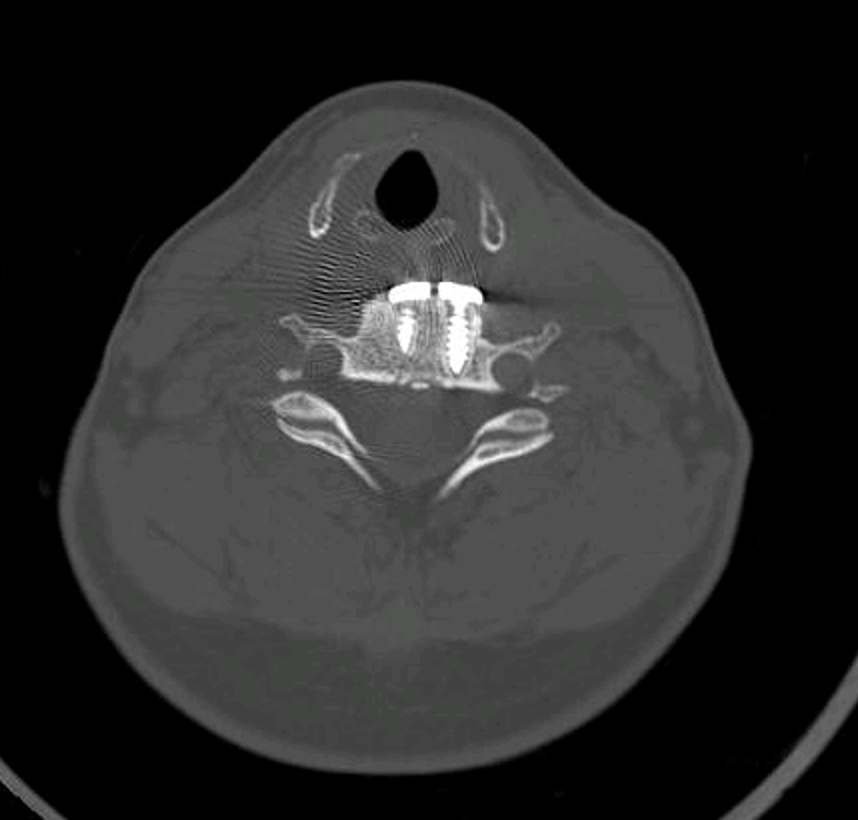

Tras hacer un estudio de la paciente mediante TAC y resonancia magnética llegamos a la conclusión que la paciente presentaba un cuadro de seudo artrosis.

Al no estar bien fijados los tornillos lo que sucede es que el tornillo se va aflojando al mismo tiempo que se come el interior de la vertebra.

Imagen TAC columna vertebral